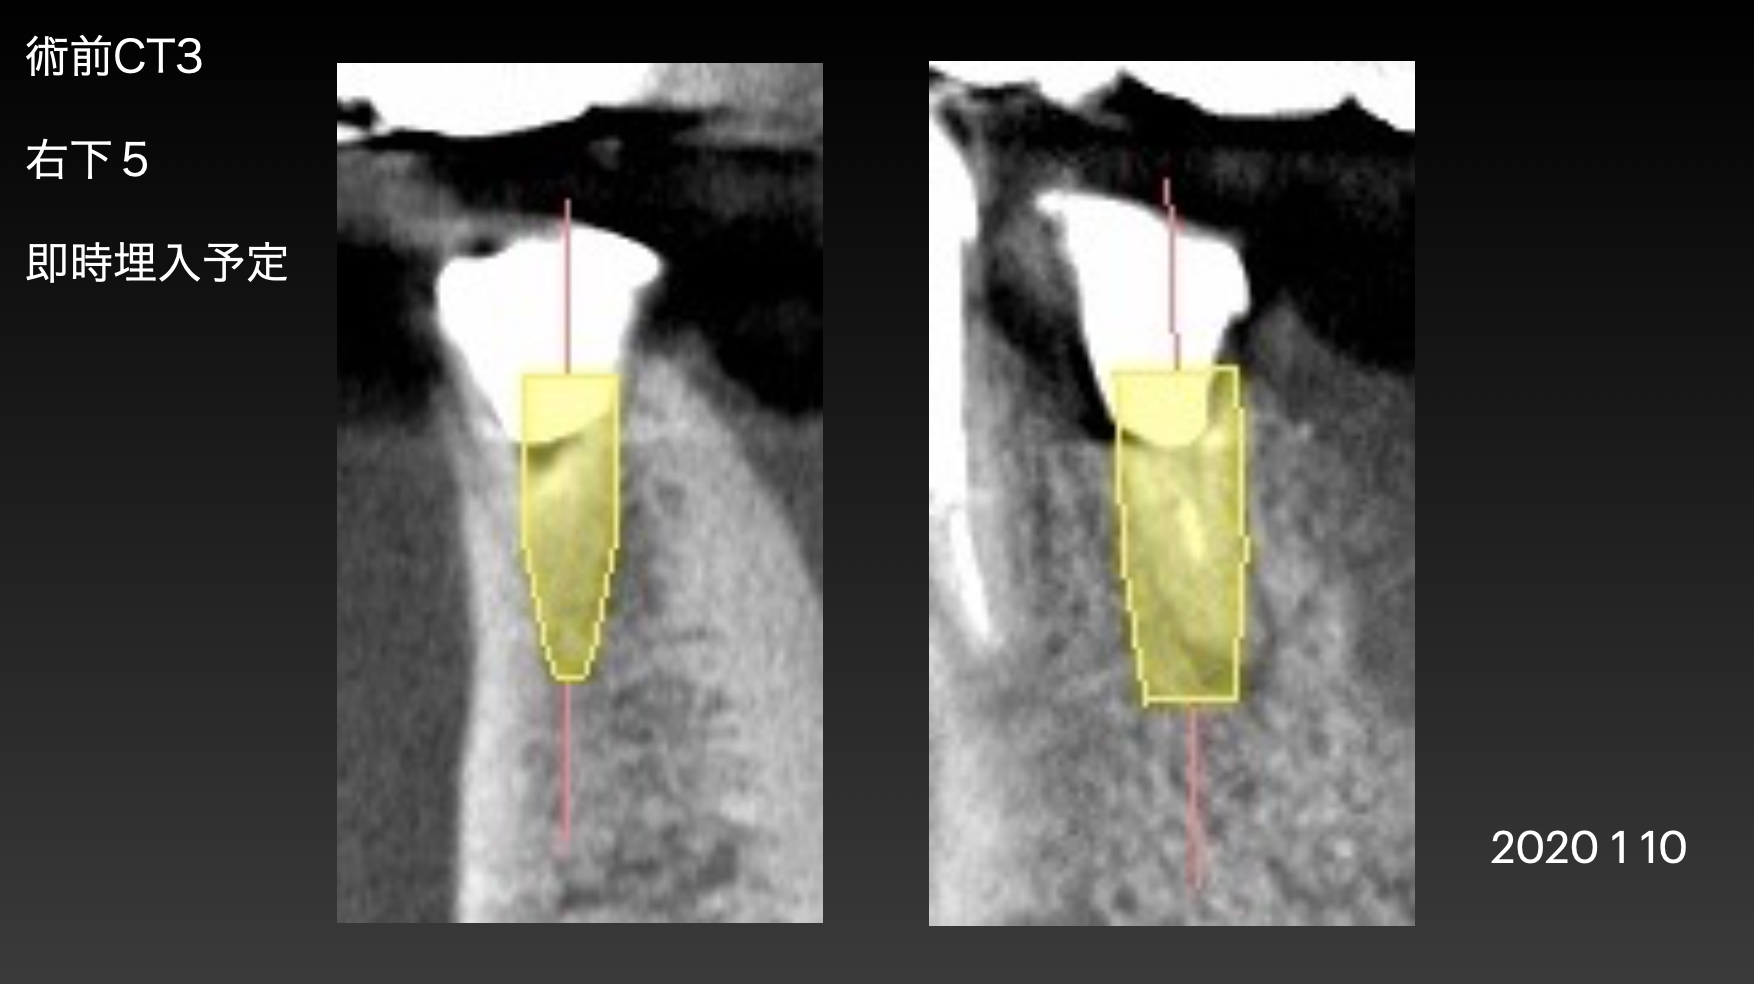

インプラント抜歯後即時埋入ができるかどうか判断します。歯の根っこの形によって、インプラントの太さや長さを変えます。また、この画像で抜く予定の歯の周囲に膿みや感染病巣がある場合は、即時でなく通常の手術プランに変更します。

この症例は2本のインプラントを並行に入れなければならない為、オーダーメイドの手術用インプラントガイドを準備しました。